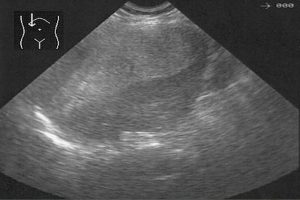

Diplomados en Ultrasonografía